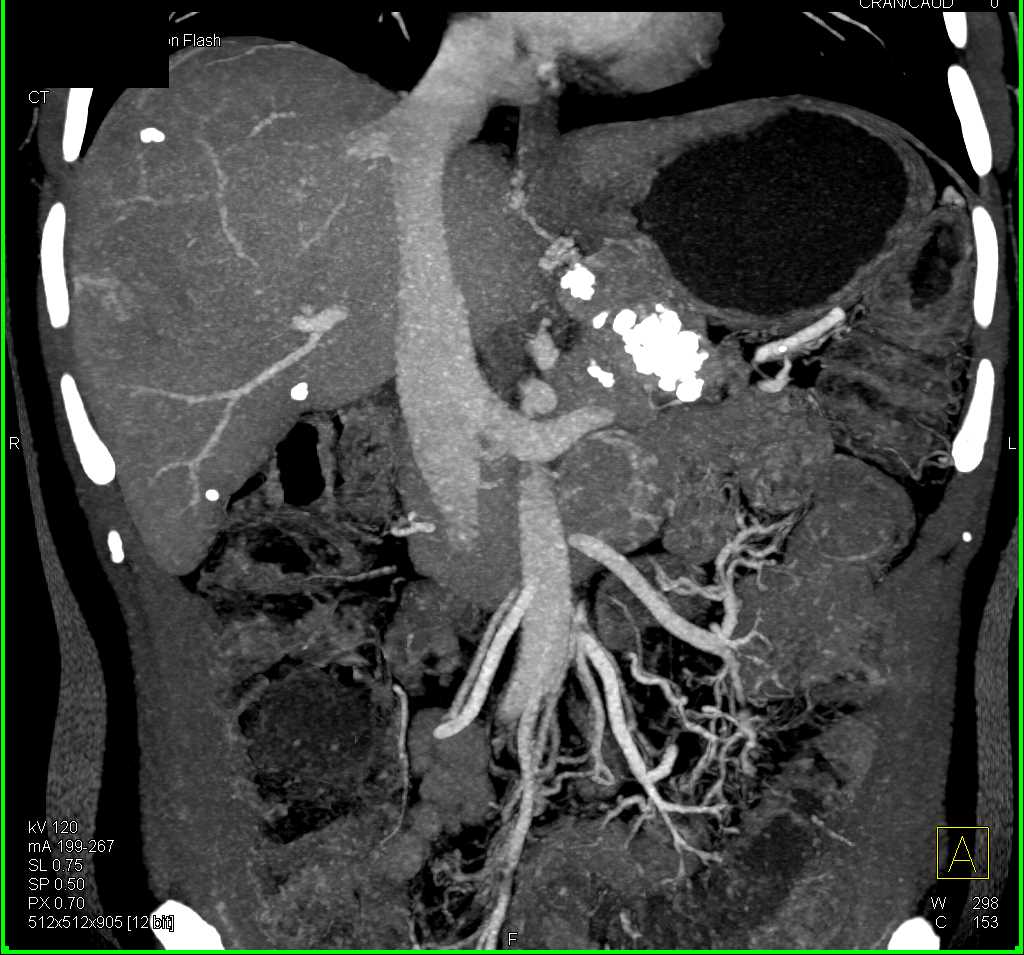

Neuroendocrine Tumor Pancreas